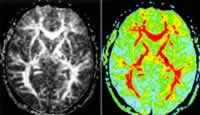

(六)腦部感染性疾病(braininfectionsdiseases)腦部感染是指細菌、病毒、寄生蟲、立克次體、螺鏇體等引起的腦及腦膜的炎症性疾病。呈急性或亞急性良性顱內壓增高,少數表現為慢性良性顱內壓增高,起病時常有感染症狀,如發熱、全身不適、血象增高等。部分病例有意識障礙、精神錯亂、肌陣攣及癲癇發作等,嚴重者數日內發展至深昏迷。有些病例可出現精神錯亂,表現為呆滯、言語動作減少、反應遲鈍或激動不安、言語不連貫,記憶、定向常出現障礙,甚至有錯覺、幻覺、妄想及譫妄。神經系統症狀多種多樣,重要特點為常出現局灶性症狀,如偏癱、失語、雙眼同向偏斜、部分性癲癇、不自主運動。其他尚可有頸項強直、腦膜刺激征等。腦脊液常有炎性改變,如腦脊液白細胞增多,蛋白量增多,或有糖或氯化物的降低,補體結合試驗陽性等。頭顱CT可見有炎性改變。